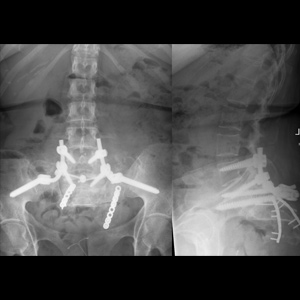

Spinal stenosis (Lumbar) Spinal stenosis (Cervical) Spinal stenosis (Thoracic) Lumbar Disc Herniation Spondylolisthesis Cervical Foraminal Stenosis Vertebroplasty Lumbar Fusion Anterior Cervical Fusion (ACDF) Posterior Cervical Fusion Thoracic Fusion Revision Lumbar Fusion Surgery Facet Joint Cyst Spinal Tumour Minimally Invasive Lumbar Fusion (XLIF) Minimally Invasive Lumbar Fusion (ALIF) Lumbar Fusion (TLIF) Thoraco-lumbar Fusion Lumbar Corpectomy Complex Lumbar Spine Surgery (Spino-pelvic fixation) Complex Cervical Spine Surgery Complex Thoracic Spine Surgery Occipito-cervical Fusion Minimally invasive surgery for thoracic disc herniation Other Related Topics